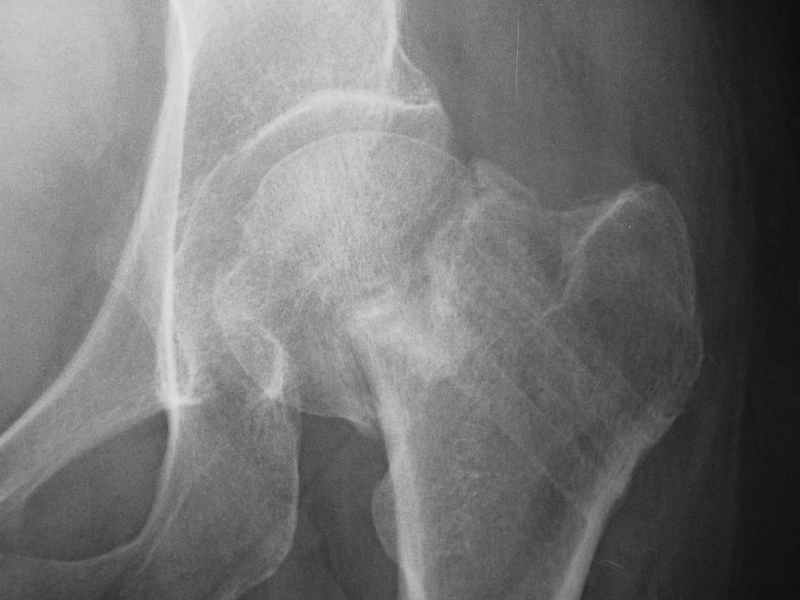

Варус тут за счет сдвига дистального отломка проксимально. Край шейки на периферическом отломке виден ведь хорошо.

Так его видно на фасном снимке.

Градусов на 25 больше.

Да как же нет, если головка сползла на 2 см дистальнее и кзади.